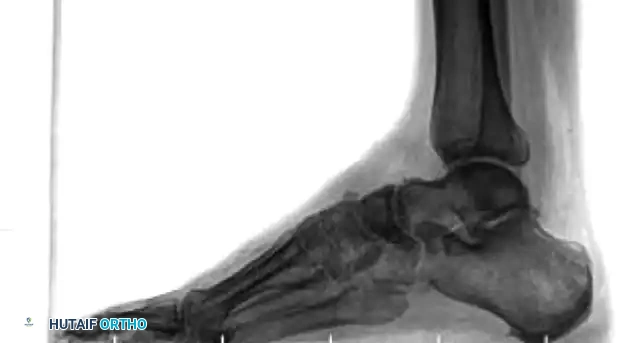

The tarsal navicular is the keystone of the medial column. Fractures here threaten the integrity of the talonavicular joint—the primary joint responsible for hindfoot circumduction. While minimally displaced fractures can theoretically be managed in a non-weight-bearing cast, true minimal displacement is exceedingly rare.

Fractures of the tarsal navicular body are classified into three distinct types based on the Sangeorzan classification system. The primary surgical goals for displaced fractures are the restoration of articular congruity and the maintenance of medial column length.

- Type I: The fracture line occurs in the coronal plane, creating a dorsal fragment that usually consists of less than 50% of the navicular body. Anteroposterior radiographs may only show a subtle double cortical shadow at the joint line.

- Type II: The primary fracture line is sagittal or oblique. The talonavicular joint is most often subluxated dorsally and medially, accompanied by adduction of the forefoot.

- Type III: Characterized by severe comminution of the navicular body. This is frequently associated with disruption of the cuneiform-navicular joint, lateral deviation of the forefoot, and concomitant injuries to the cuboid or the anterior process of the calcaneus.